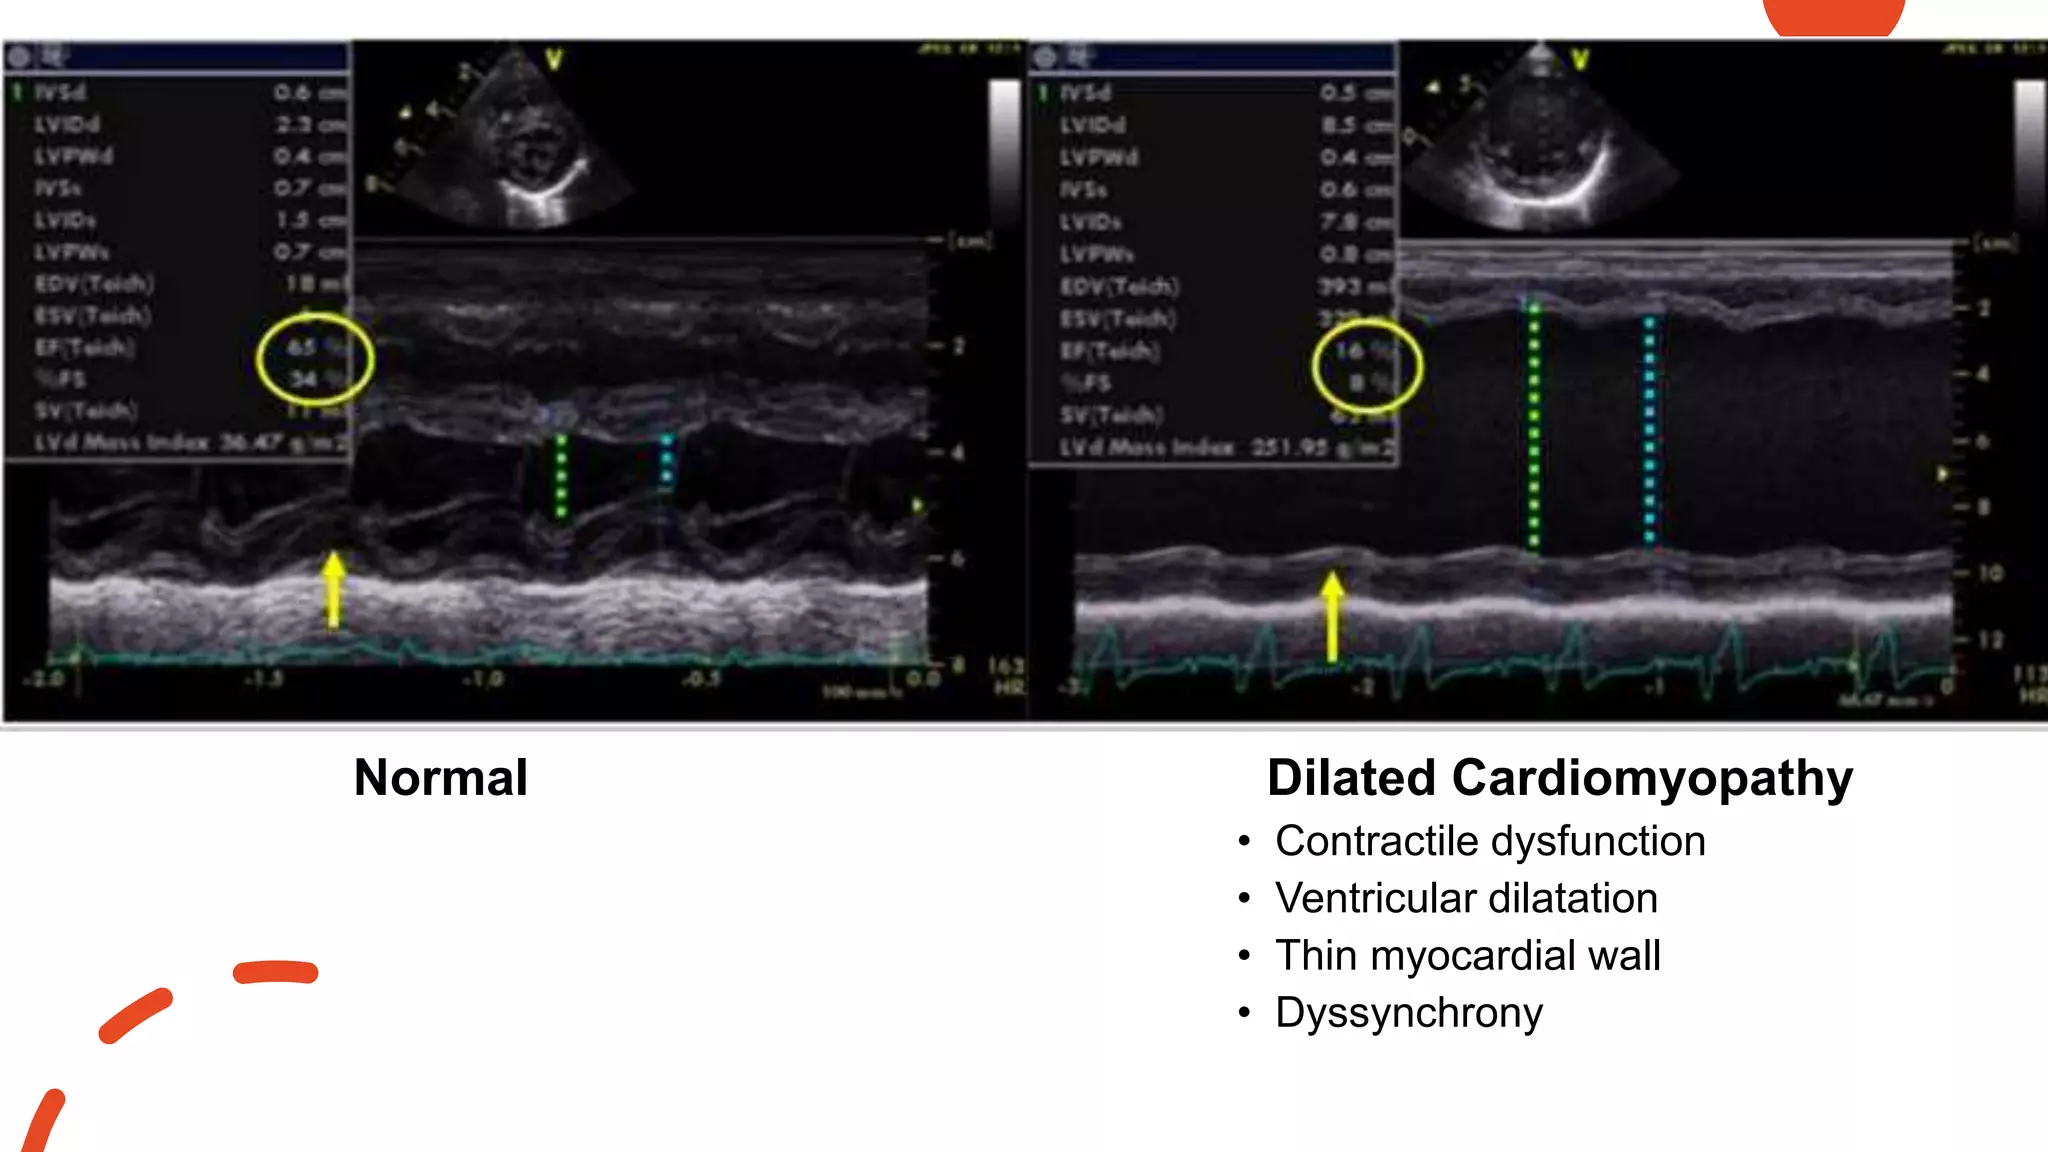

• Contractile dysfunction

• Ventricular dilatation

• Thin myocardial wall

• Dyssynchrony

Normal Dilated Cardiomyopathy

• #41 M-mode echocardiography obtained from a patient (left image) with normal left ventricular systolic function (FS = 34% and EF = 65%) and in a patient (right image) with dilated cardiomyopathy with severe left ventricular systolic dysfunction (FS = 8% and EF = 16%), LVEDD with green arrow and LVESD with blue arrow. Abbreviations: EF, ejection fraction; FS, fractional shortening; LVEDD, left ventricle end-diastolic dimension; LVESD, left ventricle end-systolic dimension.